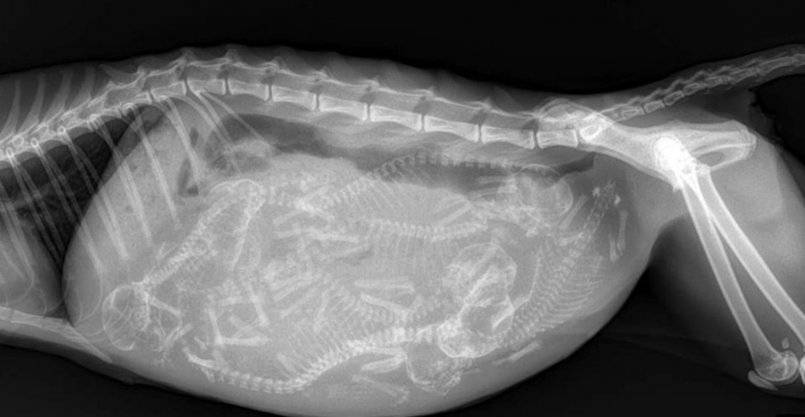

- Рентгенографию (для определения наличия асцита брюшной полости).

Выпотной (влажный) ФИП — наиболее тяжёлая клиническая форма, которая быстро приводит к летальному исходу. Она характеризуется выпотом в брюшную полость. Наряду с этим в 20% случаев присутствуют выпоты в плевральную полость и перикард, главным клиническим симптомом в таких случаях является затруднённое дыхание. Наблюдаются исхудание, анемия, лихорадка, рвота, диарея, возможно развитие перикардита, печеночной недостаточности. Может наблюдаться желтуха, особенно на поздних стадиях болезни. Поражение глаз и центральной нервной системы наблюдается в 10% случаев заболевания выпотным перитонитом. Смерть наступает в течение 1-2 месяцев.

При влажной (выпотной) форме перитонита со скоплением жидкости в брюшной полости у кота увеличивается в объеме живот. Животному становится трудно ходить. Когда кошка спрыгивает с небольшой высоты, раздается характерный звук, будто на пол упал пакет с водой.

- УЗИ или рентген. Обследование живота одним из способов помогает обнаружить воспалительные процессы и развитие поражений тканей внутренних органов. При инфекционном перитоните диагностика показывает даже небольшое скопление экссудата в полости живота.